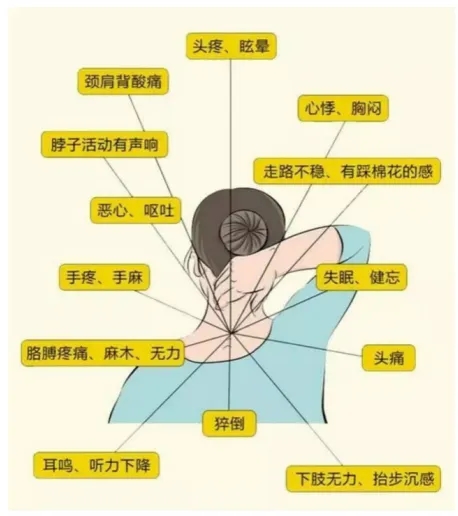

頸椎病,看似只是頸椎出了問題,但隨著病情的發展,其實會傷及全身。首先,頸椎作為脊柱中靈活性最大、活動頻率最高的節段,隨著病情的發展,勢必會影響到個人活動功能,甚至稍微一個轉頭都可能覺得不適。

其次,頸椎病有可能壓迫到神經,不僅會引起頭暈頭痛、耳聾耳鳴等癥,還可能誘發癱瘓、中風等疾病,甚至與常見的失眠、腸胃功能紊亂等都有關。